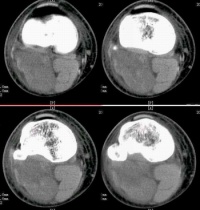

鼻咽部恶性淋巴瘤

主要为两侧气管旁和肺门淋巴结肿大。通常以气管旁淋巴结肿大为主,并且多为两侧对称性。早期可能仅表现为气管两旁上纵膈阴影轻度增宽。由于此类肿瘤生长迅速,发现病变时,多数明显肿大的淋巴结均已融合成块,使上纵膈向两侧明显增宽,轮廓清楚而呈波浪状,密度均匀。侧位胸片见肿瘤位于中纵膈上中部,即气管及肺门区,肿块边界不清楚。钱纵膈胸骨后淋巴结也常被侵及,表现为紧贴于胸骨后的圆形或椭圆形带有波浪状向后突出的阴影。

CT扫描对显示纵膈各组淋巴结肿大有特殊的优点,显著优于常规X线检查。在早期病变,纵膈轻度增宽时,CT扫描可显示肿块的部位和形态符合纵膈的肿大淋巴结,以及各组淋巴结受侵的范围,对诊断很有帮助。

何杰金病侵犯纵膈交非何杰金病更为多见,而且较易表现两侧病变大小不对称。孤立的前纵膈病变,

不伴有气管旁和肺门淋巴结异常,但常伴有颈部淋巴结肿大。这类类型的淋巴瘤在X线表现上甚似胸腺瘤,在病理上常可见在肿瘤内有残留的凶险组织。